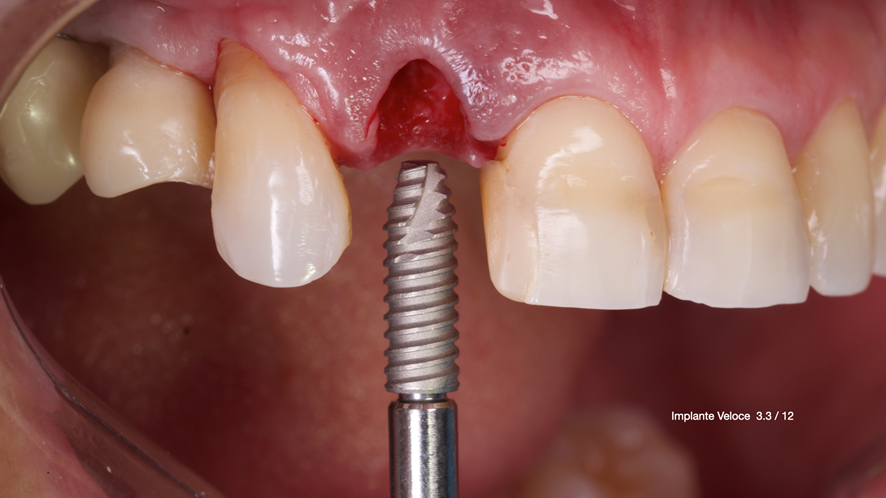

Este trabalho tem como objetivo relatar um caso clínico de exodontia minimamente invasiva de um incisivo lateral superior com fratura radicular, realizando implante imediato em alvéolo pós-extração, enxerto de tecido conjuntivo subepitelial e osso bovino liofilizado para preenchimento de GAP, prontamente à instalação de pilar reto e provisório imediato.